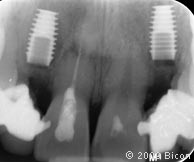

4. Радиограмма перед проведением операции.

24. Рентгеновский снимок после операции.